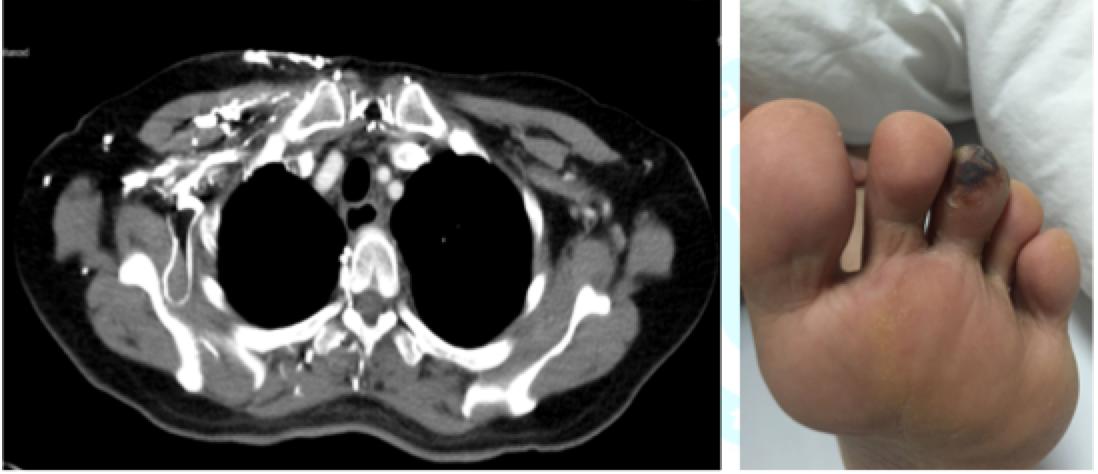

3. 三线: 2017-10-18予以培美曲塞800mg+卡铂500mg化疗,出现气促,3度骨髓抑制,4度肝功能损害。2017-10-23血液NGS:ROS1基因融合,METexon16错义突变。2017-11-22MRI脑转移病灶增多,脑膜转移。2017-11-23CT左下肺病灶缩小36%。出现左足第三趾皮色发黑,PS=2分。

4. 2017-11-17我院CT引导下行左下肺病灶肺穿刺活检,病理:浸润性腺癌;ROS1基因有断裂57%;EGFR、ALK-;c-MET、PD-L1结果未出。2017-11-23外周血NGS:ROS1融合,METexon16错义突变。